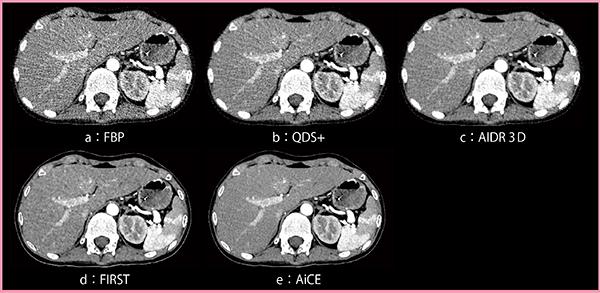

図1は8.7mGyで撮影した腹水貯留のある症例(症例1)で,FBP(a)と比較し, QDS+(b)では臓器の構造境界がボケることなくノイズが大幅に低減されている。一方,1.5mGyの低線量で撮影した小児腹部CTのアキシャル画像(症例2:図2)では,QDS+の画像(b)はFBP(a)よりは良好であるものの,ノイズ低減効果は弱く,ストリークアーチファクトも残存している。

図1,2におけるQDS+(b)とAIDR 3D(c)の画像を比較すると,QDS+で残存していたノイズが,AIDR 3Dではより高いレベルで低減されており,ストリークアーチファクトも大幅に低減されている。

図1,2におけるAIDR 3D(c)とFIRST(d)の画像を比較すると,FIRSTの方が明らかにノイズやアーチファクトが低減されている。ただし,図2をよく見ると,FIRST(d)では肝臓内の軟部組織のテクスチャが粗く,構造が視認しづらい。

図1,2におけるFIRST(d)とAiCE(e)の画像を比較すると,AiCEの方がより高レベルなノイズ低減を実現している。また,FIRSTで問題となっていた軟部組織のテクスチャの粗さも,AiCEでは問題なく,あたかも高線量で撮影したかのような,非常にきめ細やかな画質が得られている。

図2 1.5mGyで撮影した小児腹部CTのアキシャル画像(症例2)